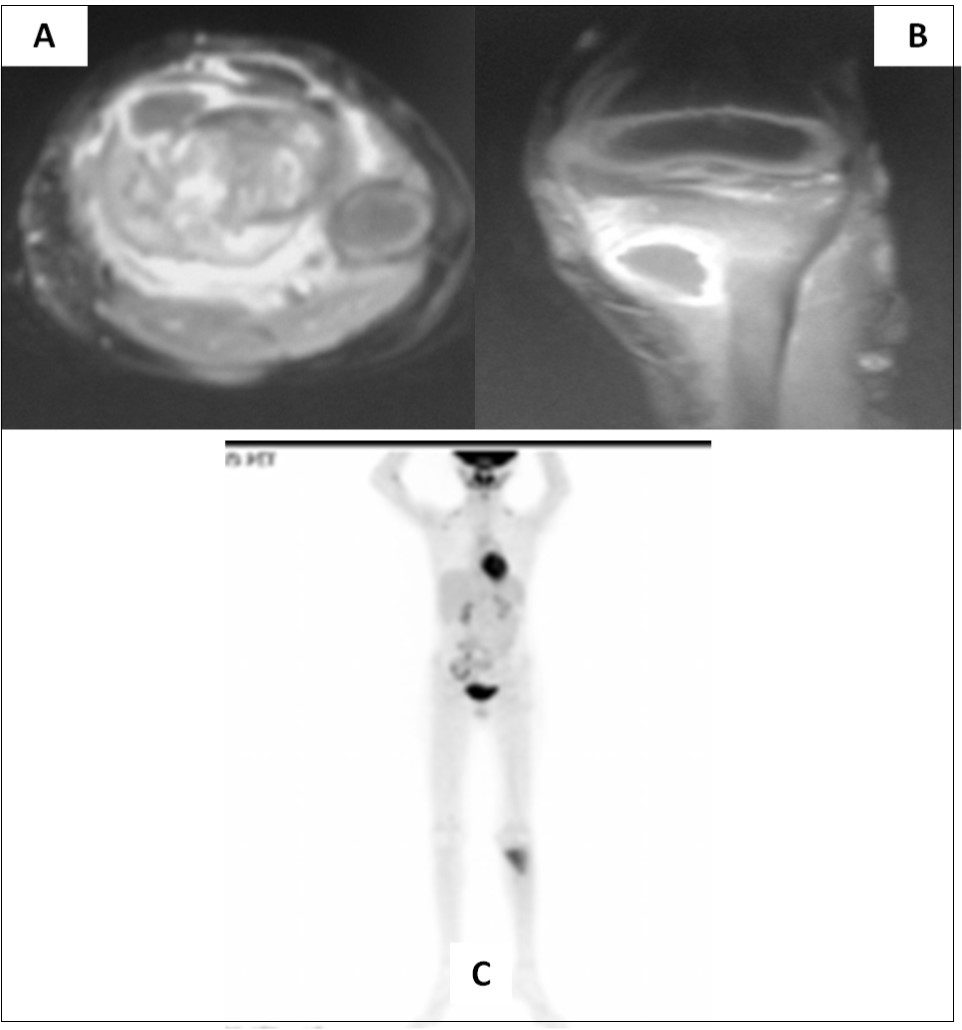

Two and half years after completion of therapy (just over 3 years from initial diagnosis), the child presented with pain in the left lower limb following a trivial injury. Local radiograph showed a large lytic/sclerotic lesion in the proximal left tibia. MRI of the left lower extremity (Figure 2A-B) confirmed the presence of this lytic/sclerotic lesion arising from the proximal tibial metaphysis with significant invasion of the adjacent soft tissues. The lesion was isointense on T1-weighted images, heterogeneously hypointense on T2-weighted images, hyperintense on STIR images with moderate post-contrast enhancement. Whole-body 18-F-fluoro-deoxy-glucose positron emission tomography/computed tomography (FDG-PET/CT) showed increased radiotracer uptake limited to the mass lesion in the proximal left tibia with a maximum standardized uptake value (SUVmax) of 6.28 suggestive of localized metabolically active tumor. There were no other areas of abnormal tracer uptake anywhere in the body ruling out disseminated disease (Figure 2C). Neuraxial imaging at this time did not reveal any local recurrence in the posterior fossa or leptomeninges confirming that the index cancer was controlled. The differential diagnosis was between second primary bone neoplasm with extensive soft tissue component versus solitary metastasis from medulloblastoma.

Figure 2.Axial (A) and coronal (B) MRI sections of left proximal tibia showing a large soft tissue component in addition to the lytic/sclerotic bony lesion. Whole body FDG-PET/CT showing increased tracer uptake localized to this lesion (C) with no significant abnormal uptake elsewhere in the body

Axial (A) and coronal (B) MRI sections of left proximal tibia showing a large soft tissue component in addition to the lytic/sclerotic bony lesion. Whole body FDG-PET/CT showing increased tracer uptake localized to this lesion (C) with no significant abnormal uptake elsewhere in the body